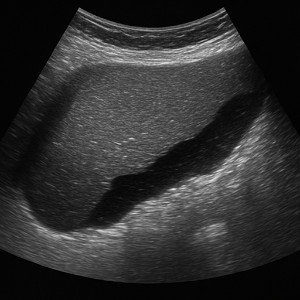

신장 결석, 신부전, 낭종

콩팥에 생긴 작은 돌들은 초음파에서 반짝이며 그림자를 동반해 쉽게 보일 수 있어요. - 신부전 (수신증 등)

소변이 막혀서 신장이 붓는 상태를 ‘수신증’이라고 하는데요, 초음파로 신장의 부종이나 이상을 확인할 수 있어요. - 신장 낭종이나 종양

주머니처럼 생긴 낭종이나 덩어리가 있으면 초음파로 확인 가능해요.